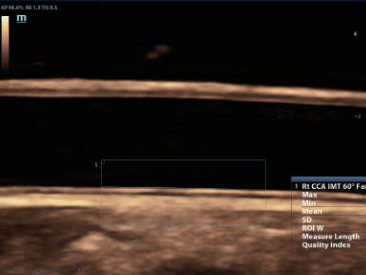

–Γ–Ω–Β―Ü–Η–Α–Μ–Η–Ζ–Η―Ä–Ψ–≤–Α–Ϋ–Ϋ―΄–Ι –Η–Ϋ―²–Β―Ä–≤–Β–Ϋ―Ü–Η–Ψ–Ϋ–Ϋ―΄–Ι –¥–Α―²―΅–Η–Κ

–Γ–Ω–Β―Ü–Η–Α–Μ―¨–Ϋ–Ψ ―¹–Κ–Ψ–Ϋ―¹―²―Ä―É–Η―Ä–Ψ–≤–Α–Ϋ–Ϋ―΄–Ι –¥–Α―²―΅–Η–Κ –¥–Μ―è –Ω―Ä–Ψ–≤–Β–¥–Β–Ϋ–Η―è –Η–Ϋ–≤–Α–Ζ–Η–≤–Ϋ―΄―Ö –Ω―Ä–Ψ―Ü–Β–¥―É―Ä –Η –Η―¹―¹–Μ–Β–¥–Ψ–≤–Α–Ϋ–Η–Ι –≤ 2D ―¹ –Φ–Η–Ϋ–Η–Φ–Α–Μ―¨–Ϋ–Ψ–Ι ―¹–Μ–Β–Ω–Ψ–Ι –Ζ–Ψ–Ϋ–Ψ–Ι, –Α ―²–Α–Κ–Ε–Β –Κ–Ψ–Ϋ―²―Ä–Α―¹―²-―É―¹–Η–Μ–Β–Ϋ–Ϋ―΄―Ö –Η―¹―¹–Μ–Β–¥–Ψ–≤–Α–Ϋ–Η–Ι;